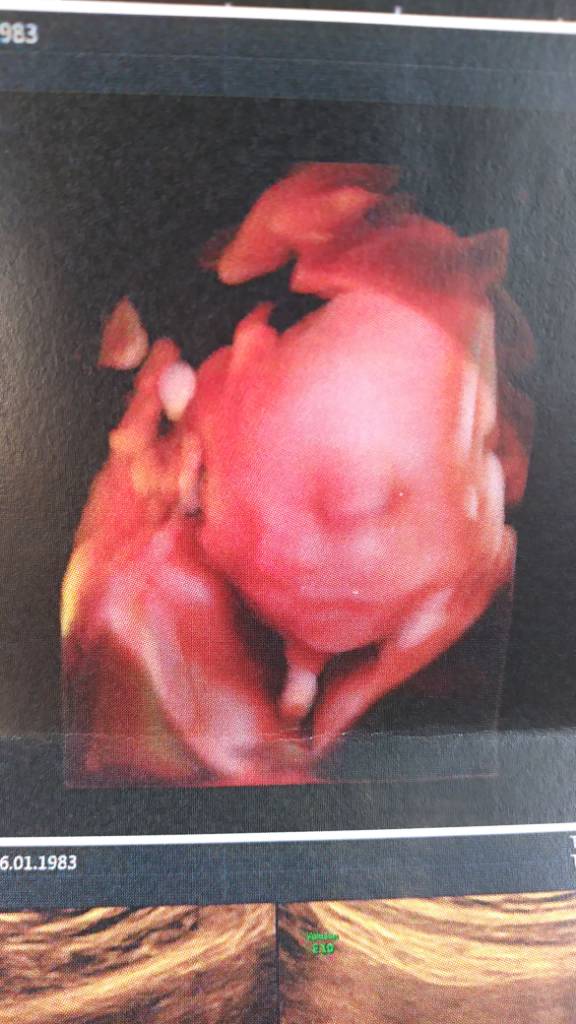

Poprzednie wizyty też tam miałaś? Widziałam jakaś reklamę ich sprzętu do 3d, ale nie pamiętam jak to się fachowo nazywało, ale zupełnie inaczej wygląda niż na standardowym usg.

Reklamy nie widziałam żadnej, ale sprzęt mają niezły, to fakt ;)

Z drugiego prenatalnego:

Ooo właśnie o to mi chodziło :) Zupełnie inaczej te zdjęcia wyglądają niż u mnie.